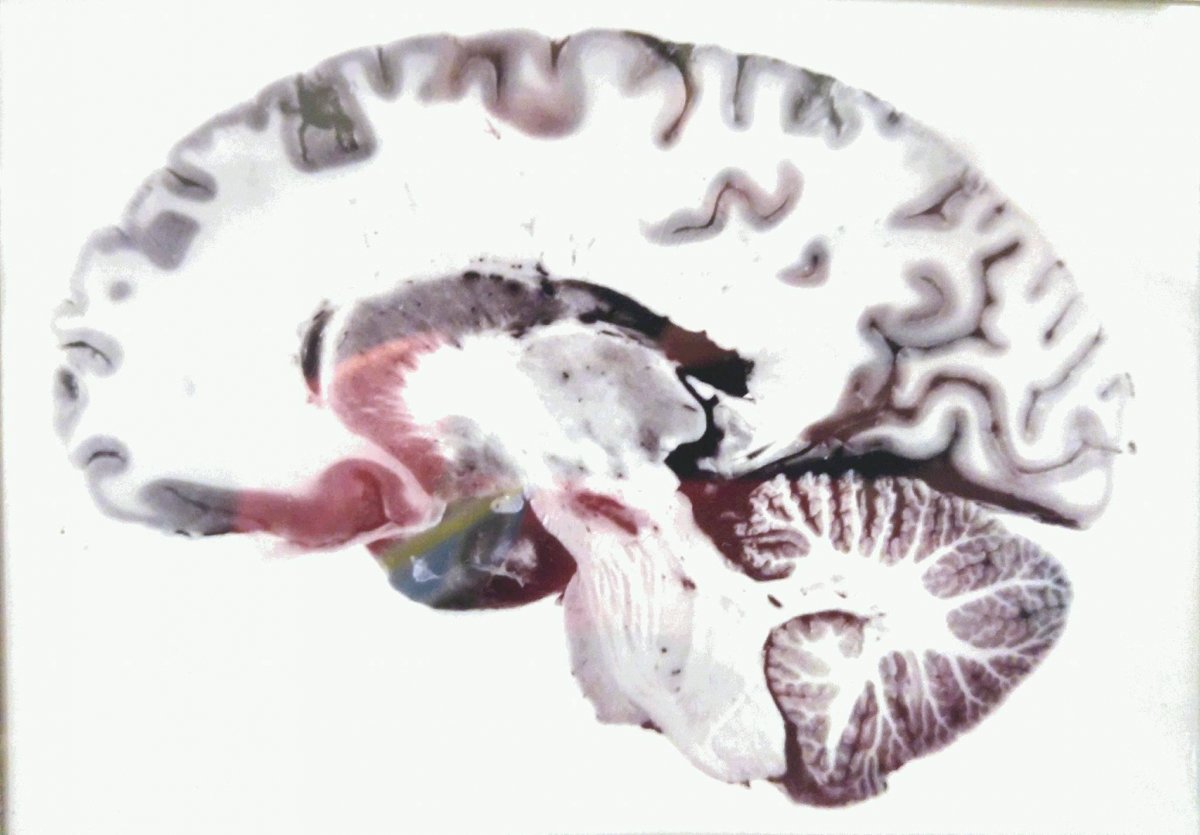

The process of plastinations follows the idea that if you inject a body with plastic to coat the cells then it will be preserved in its original state - this follows the same idea as coating the outside in a thick layer of plastic but allows the detail of the organ to be seen for what it is and in closer detail. I find these works hugely interesting and enlightening and has really allowed me to see the shape and textures of the muscle and nerve tissues. I dislike the fact that the pieces are stationary because as biological organisms we are continually moving and changing whereas here they have only captured one point in time, therefore a lot of work is needed in order to understand a biological sequence such as an electric impulse. This makes a lot of Dr. Hagens work redundant for my own use. Even though this may be the case the works ( like the plastinated brain) have provided a solid understanding of if shape and use - this is something that is essential to my work and without wich I could not proceed. I hope to meet similar standards of work in my project - including things like biological accuracy and aesthetic and natural symmetry (not quite exact). Looking at these bodies has pushed me to work with real organs and to study them fully.

The organs such as the brain and heart are more accurately portrayed when preserved with the method of plastination. This is because it retains the detail of each tissue while also keeping its three dimensional shape. This has shown its importance as when resin is used for the same purpose the original organ can not be touched. Plasination allows the original organ to show in its full glory meaning that it can actually be touched and held a very important part of learning and understanding.